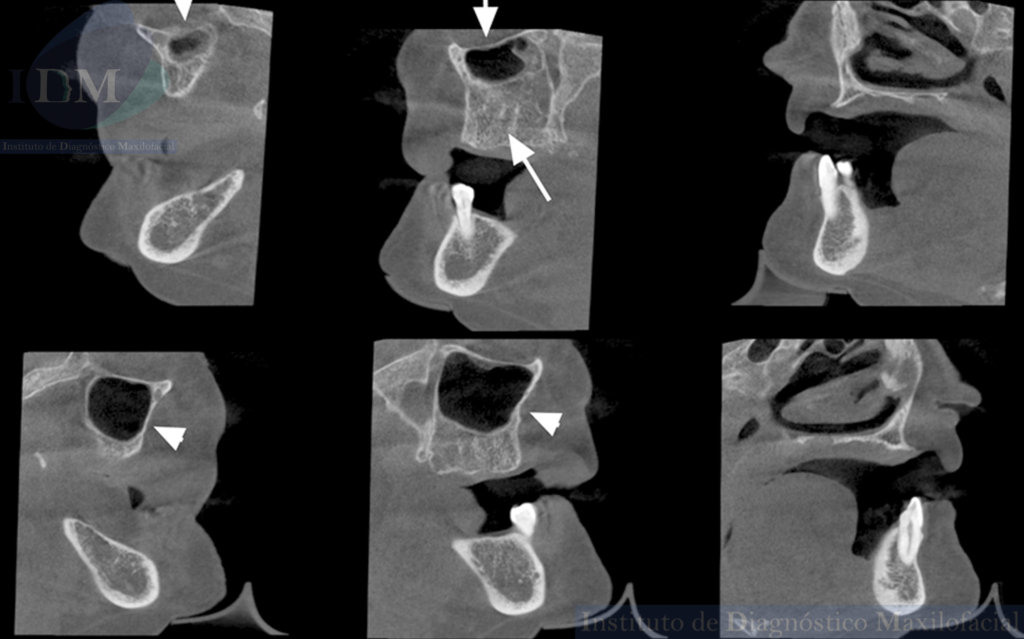

A la evaluación de la tomografía computarizada de haz cónico de campo mediano se observa la disminución de la longitud cefalo caudal y antero posterior del seno maxilar del lado izquierdo en comparación a su contralateral (visto en los cortes coronales y axiales respectivamente).

Asimismo, se observa el engrosamiento de la mucosa antral a predominio de la pared posterior que a su vez presenta una imagen hiperdensa de forma irregular compatible con probable Antrolito. Finalmente, en zonas edéntulas de premolares y molares del segundo cuadrante se observa el trabeculado óseo característico del maxilar superior que debería estar ocupado por el seno maxilar.

CORTES SAGITALES